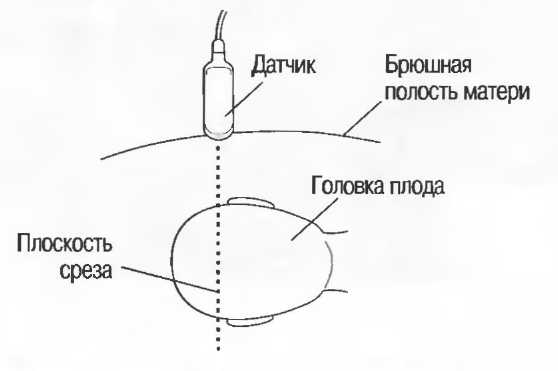

При поперечном сканировании изображение на экране монитора может перевернуться таким образом, что левая сторона пациента окажется с правой стороны экрана. Несмотря на то что на датчике имеется индикатор положения, важно перед исследованием визуально проверить соответствие стороны датчика соответствующей стороне получаемого изображения. Лучше всего это сделать, поместив палец на один конец датчика и посмотрев, с какой стороны экрана получится его изображение. При неправильной ориентации нужно развернуть датчик на 180" и проверить снова (рис. 8а). На продольных срезах голова пациента должна определяться на экране слева, а ноги—справа.

Рис.8а. Палец на датчике должен давать изображение на соответствующей стороне экрана Если стороны не совпадают, поверните датчик на 180°.

Рис.8б. Два аксиальных среза головки плода, развернутые на 180°. Перед проведением исследования ориентация изображения на экране должна быть проверена, как показано на рис. 8а.